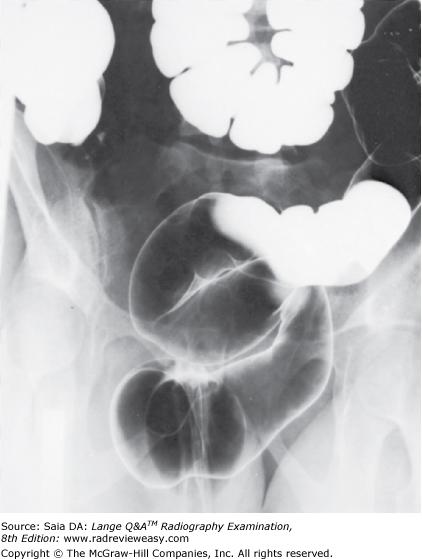

Which of the following statements referring to the images below is (are) correct?

- Image A was performed AP.

- Image B was performed AP.

- The AP image was obtained using ureteral compression.

2 only